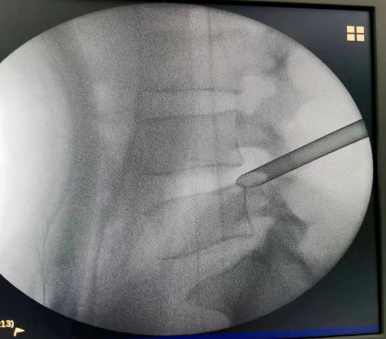

手术经过:术前仔细阅片,精确定位手术靶点部位、规划手术路径、测量通道长度、头尾倾角度。C臂透视定位、局部麻醉、穿刺建立通道、环锯进行关节突成形,连接椎间孔镜系统、椎间盘摘除、神经根管探查减压、侧隐窝减压、彻底检查无卡压后关闭伤口。手术成功,患者术后3天康复出院。

术中穿刺及关节突成形